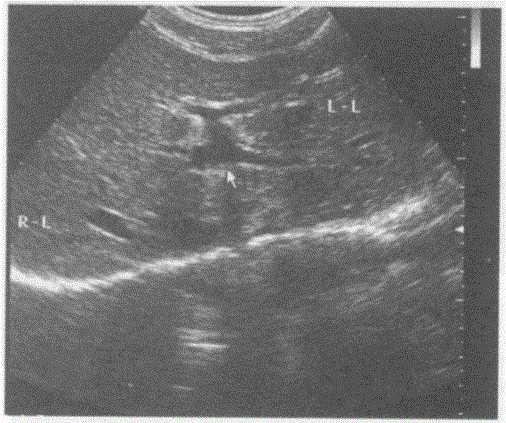

问题 下图是肝脏横切正常超声图像,请回答箭头所指部位的解剖名称:

选项 A.门静脉左外下支 B.门静脉左支横部 C.门静脉左外上支 D.门静脉左支矢状部

答案 D